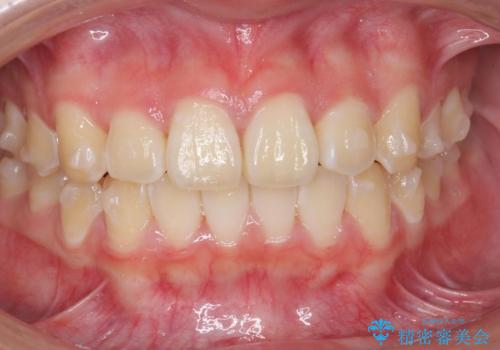

前歯のがたつき気になる。インビザラインモデレート

- 前歯のがたつきが気になるとの事で来院。

マウスピース矯正希望でしたのでインビザラインモデレートで治療を行いました。

がたつきが無くなり満足して頂けました。